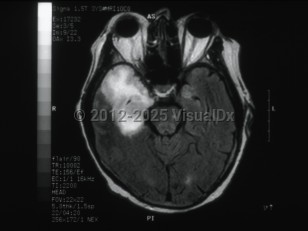

Clinically, patients typically present with focal neurologic signs that have been present for <1 week. In most cases of HSV encephalitis, the temporal lobe of the brain, usually unilateral, undergoes necrosis, and clinical findings reflect the areas of the brain that are affected. They include altered levels of consciousness, behavioral changes, focal cranial nerve deficits, ataxia, aphasia, and seizures. The majority of patients will also present with fever. The behavioral changes most commonly associated with HSV encephalitis are hypomania (including elevated mood, excessive animation, hypersexuality, and decreased sleep requirements), amnesia, and Klüver-Bucy syndrome, which is a behavioral syndrome that involves loss of typical anger and fear responses and increased sexuality. The Klüver-Bucy syndrome is thought to be associated with the proclivity of HSV encephalitis for the temporal lobes and limbic system structures. More rarely, HSV encephalitis can present as a brainstem syndrome and can result in the syndrome of inappropriate antidiuretic hormone secretion (SIADH).